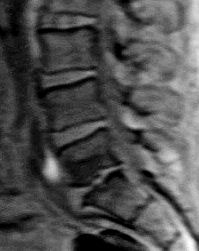

Genau das meinten Herr Doktor, Facharzt für Orthopädie, aktiver Contender-Segler, als er mir die herrlichen

MRT-Aufnahmen meiner Wirbelsäule zeigte -

- groß, klar, kontrastreich, eine Augenweide für jeden klassischen Fotografen.